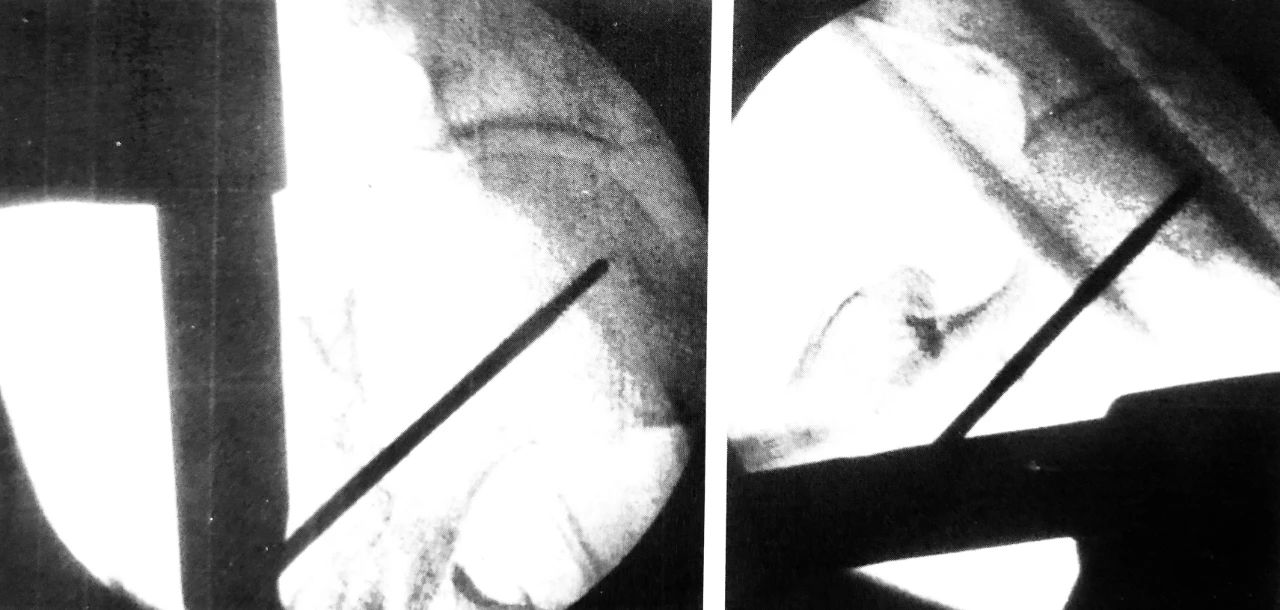

肱骨逆行髓内钉,左图为入钉口置备,右图为穿入多根弹性髓内钉